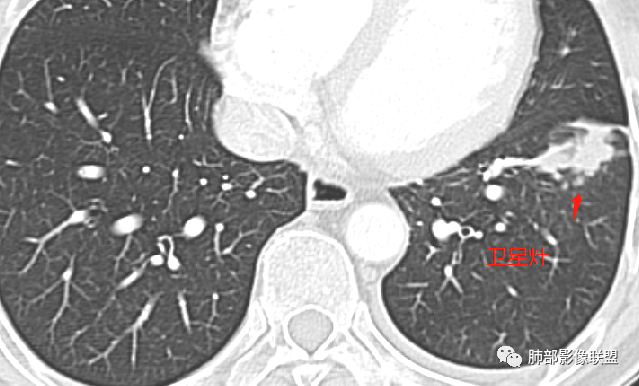

左肺下叶前基底段肿块,分叶状,边缘平直凹陷,部分膨隆。支气管进入后截断,宽基底与胸膜相连,内部坏死,周围有小卫星灶,强化见坏死区周围环形高密度,首先考虑良性,肉芽肿,结核?鉴别腺癌。

既往胃肾肿瘤。左下肺病灶直边,凹陷,支气管进入并有截断,宽基底与胸膜相连,内部有囊圆形坏死,旁边有卫星灶,考虑良性,肉芽肿,恶性,腺癌转移待除

反正直接考虑恶性风险大,理由:1、年龄,性别未提供,2、无CT旧片对照,胸片提示三个月前多发小结节,现在的CT是肿块样改变,变化这么快?整体边缘虽有膨隆,但更多是平直,桃尖。3、这个胸膜栽桩只能说可能,不能说肯定(层面不够)。4、周围的GGO样改变与主病灶关系不确切,疑似卫星灶。5、增强这个坏死情况三不像。6、纵隔淋巴结是否肿大?没提供相应层面。

3月前左肺中下野可见结节灶,现CT可见沿支气管走形融合成团片灶,近端支气管进入后截断,病灶整体以平直收缩为主,局部膨隆,与胸膜呈糊墙样改变,病灶周边可见结节,总体分析病灶是结节融合形成,远端大近端小,符合支气管爬行征,强化后其内可见多发低强化区,低强化边界不清,其内未见血管,首先考虑炎性病灶结核,隐球菌分布不符合,但是也可以有,另外恶性不能排除,建议排查结核、隐球菌,如不能明确,穿刺活检是必要的!